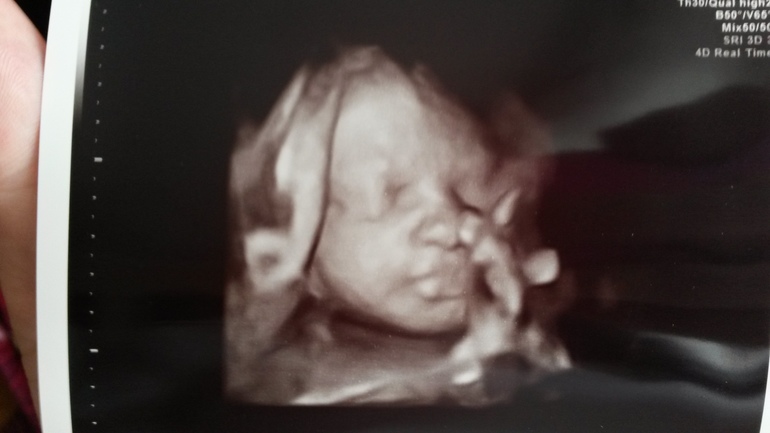

Ложусь...А она вообще не шевелится!!!Пофиг ей и на чай и на шоколадку!Она спит!!!Начинаю чуть ли не со слезами просить чтобы убрала ножки,ручка тем временем уже на лбу была,ведь мы с папой ехали так далеко в надежде на фото и видео,не хочется уезжать с пустыми руками...Неа,так ничего и не помогло!Спала красавица только иногда заглатывая вкусные воды)))В итоге все же засняли нам видео!!!!!

Были моменты когда чуть убирала ото лба ножки)))Тогда и засняли)))Моя радость!Моё солнышко!!!Я сегодня самая счастливая на свете!!!

И личико моей красавицы!!!